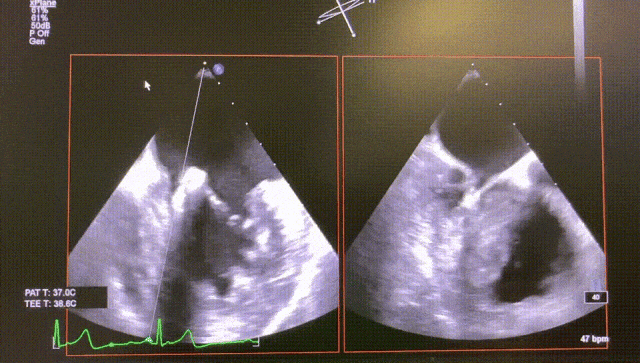

The patient is a 72-year-old female with mitral valve P3 prolapse and severe mitral regurgitation. After evalsuation, the patient was suitable for transcatheter mitral edge-to-edge repair (TEER) using the DragonFly™ system.

The procedure was uneventful, with only one XW0612 mitral clip implanted in P3 position to close the leaflet. The patient's regurgitation decreased with pulmonary venous regurgitation improved, and the mitral valve pressure difference was 1 mmHg, significantly improving the patient's cardiac function.

Before

After